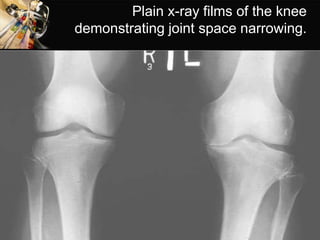

• OTHER RADIOGRAPHIC TESTS- PLAIN RADIOGRAPHIC FILMS

 Joint space narrowing, appearance of osteophytes in moderate

disease.

 Abnormal alignments of joints and joint effusion in later disease.

Physical findings of joint enlargement

Plain x-ray films of the knee

demonstrating joint space narrowing.